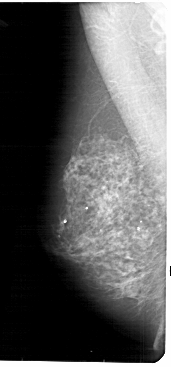

RIGHT_CC LINES 5131 PIXELS_PER_LINE 2251 BITS_PER_PIXEL 12 RESOLUTION 43.5 OVERLAY

FILE: A_1831_1.RIGHT_CC.OVERLAY

TOTAL_ABNORMALITIES 1

ABNORMALITY 1

LESION_TYPE CALCIFICATION TYPE PUNCTATE DISTRIBUTION CLUSTERED

ASSESSMENT 4

SUBTLETY 1

PATHOLOGY BENIGN

TOTAL_OUTLINES 1

BOUNDARY